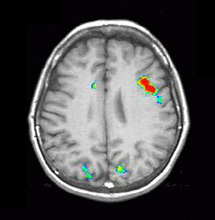

| Activación |

El hemisferio izquierdo muestra activación predominante. Se activaron las siguientes áreas: Área de Broca, porción posterior izquierda de las circunvoluciones temporales inferiores y medias (área 37 de Brodmann), parietal izquierdo y corteza premotora izquierda. Se observa una amplia activación en la cara inferior de los lóbulos occipitales. La activación principal en la derecha está ubicada en la cara inferior del lóbulo frontal (área 11 de Brodmann), un hallazgo observado constantemente en este paradigma. |